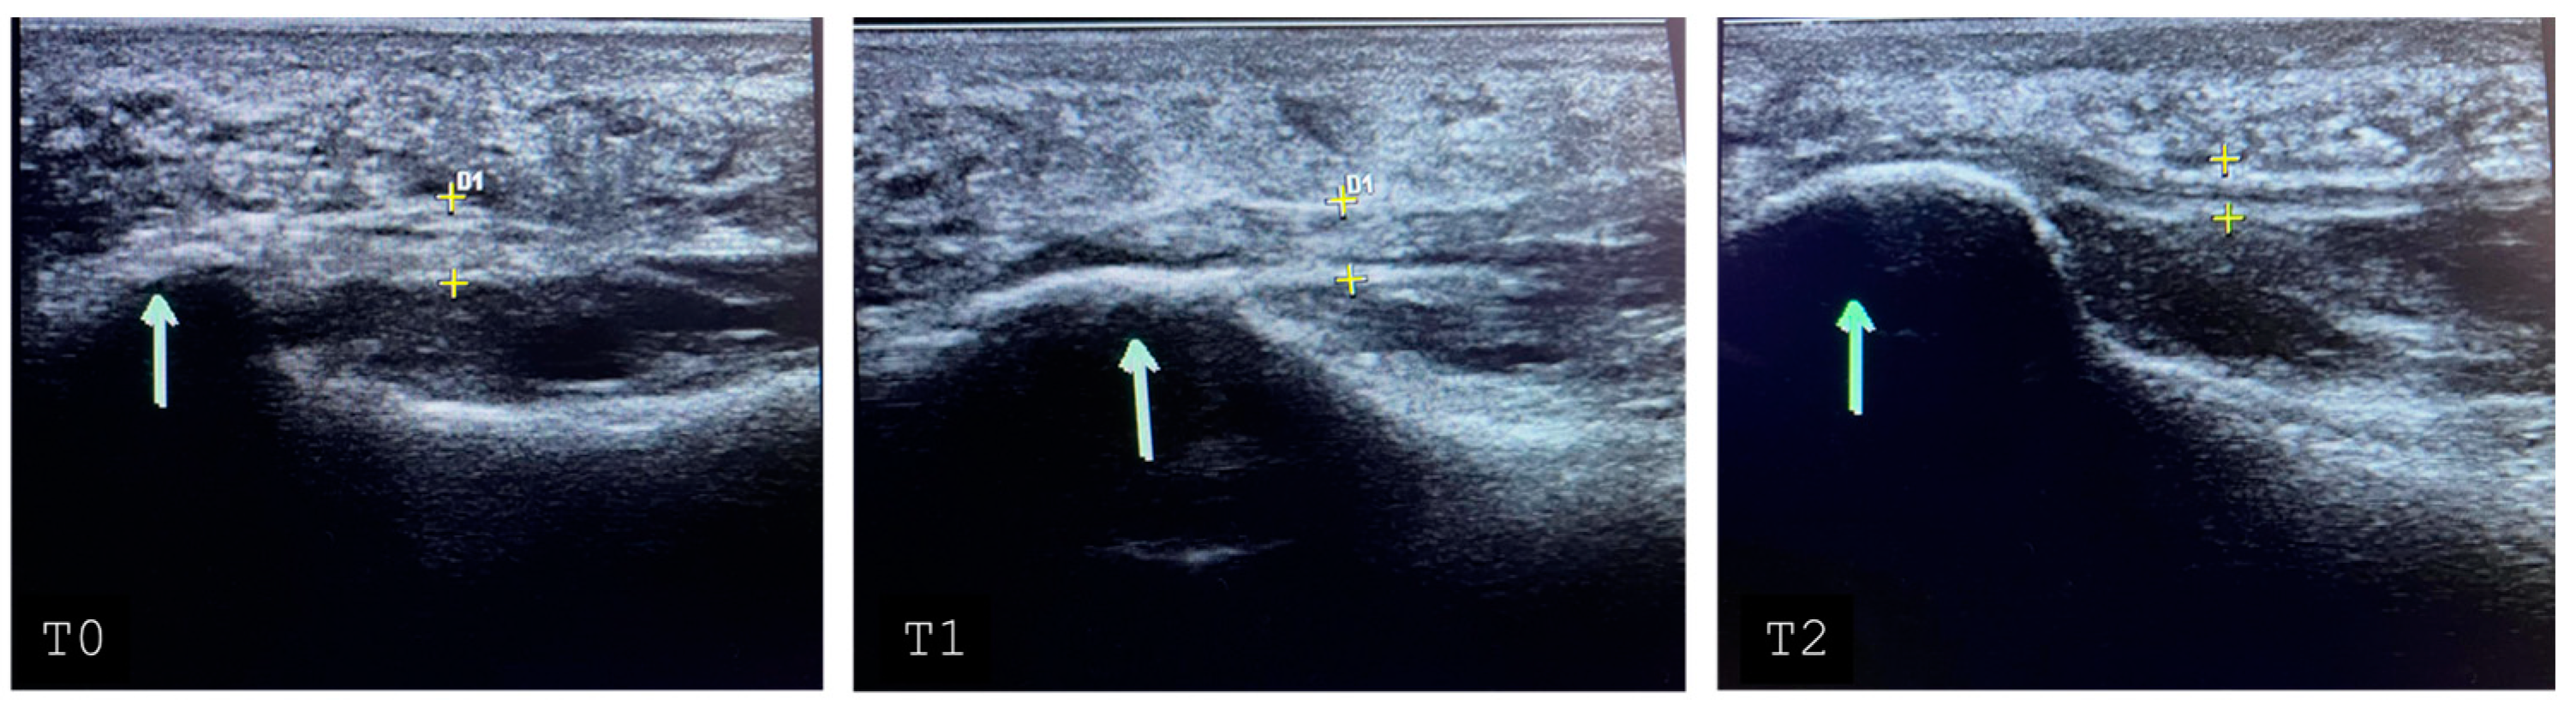

| Presence of bone edema | No | 23 | 48.94 |

| Yes | 24 | 51.06 | |